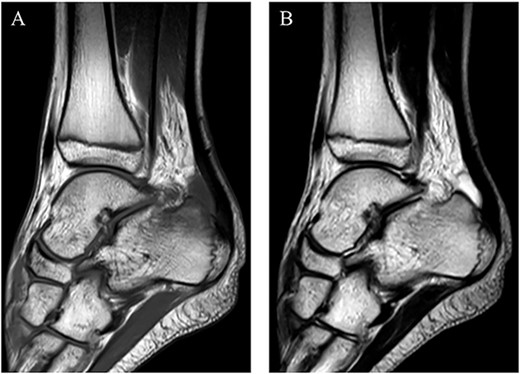

A 14-year-old male soccer player who belonged to a junior high school soccer club complained of right heel pain without trauma histories when he was playing a soccer. He had no medical history. He visited a local clinic and was treated with conservative treatment including rest, a non-weightbearing splint and anti-inflammatory medication for 4 days. However, his symptoms got worse, and so he visited our hospital. At the first visit to our hospital, physical examination revealed redness, local heat, swelling and tenderness around the insertion of the Achilles tendon. Also, his right foot was in equinus position, and it was difficult to correct his foot position accurate due to his heel pain (Fig. 1). Plain radiographs showed no abnormal findings (Fig. 2). Magnetic resonance imaging (MRI) demonstrated a low intensity signal on T1-weighted images and a high intensity signal on T2-weighted images in the retrocalcaneal bursa (Fig. 3). Laboratory examination revealed 2.1 mg/dL of C-reactive protein and 7.5 cells × 103/μL of white blood cell count. In addition, ultrasound-guided needle aspiration of the retrocalcaneal bursa resulted in 3 ml of purulent material and in which was positive for methicillin-susceptible Staphylococcus aureus (MSSA). We diagnosed him with septic RB caused by MSSA and started to treat with conservative treatment including a non-weightbearing splint and intravenous antibiotics therapy using cefazolin (6000 mg per day). However, his symptoms and laboratory results did not improve at 4 days after starting intravenous antibiotics therapy, and so we applied hindfoot endoscopic bursectomy for him.

MRI demonstrated a low intensity signal (arrow) on (A) T1-weighted images and a high intensity signal (arrow) on (B) T2-weighted images in the retrocalcaneal bursa.